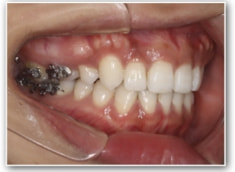

治療開始1年後